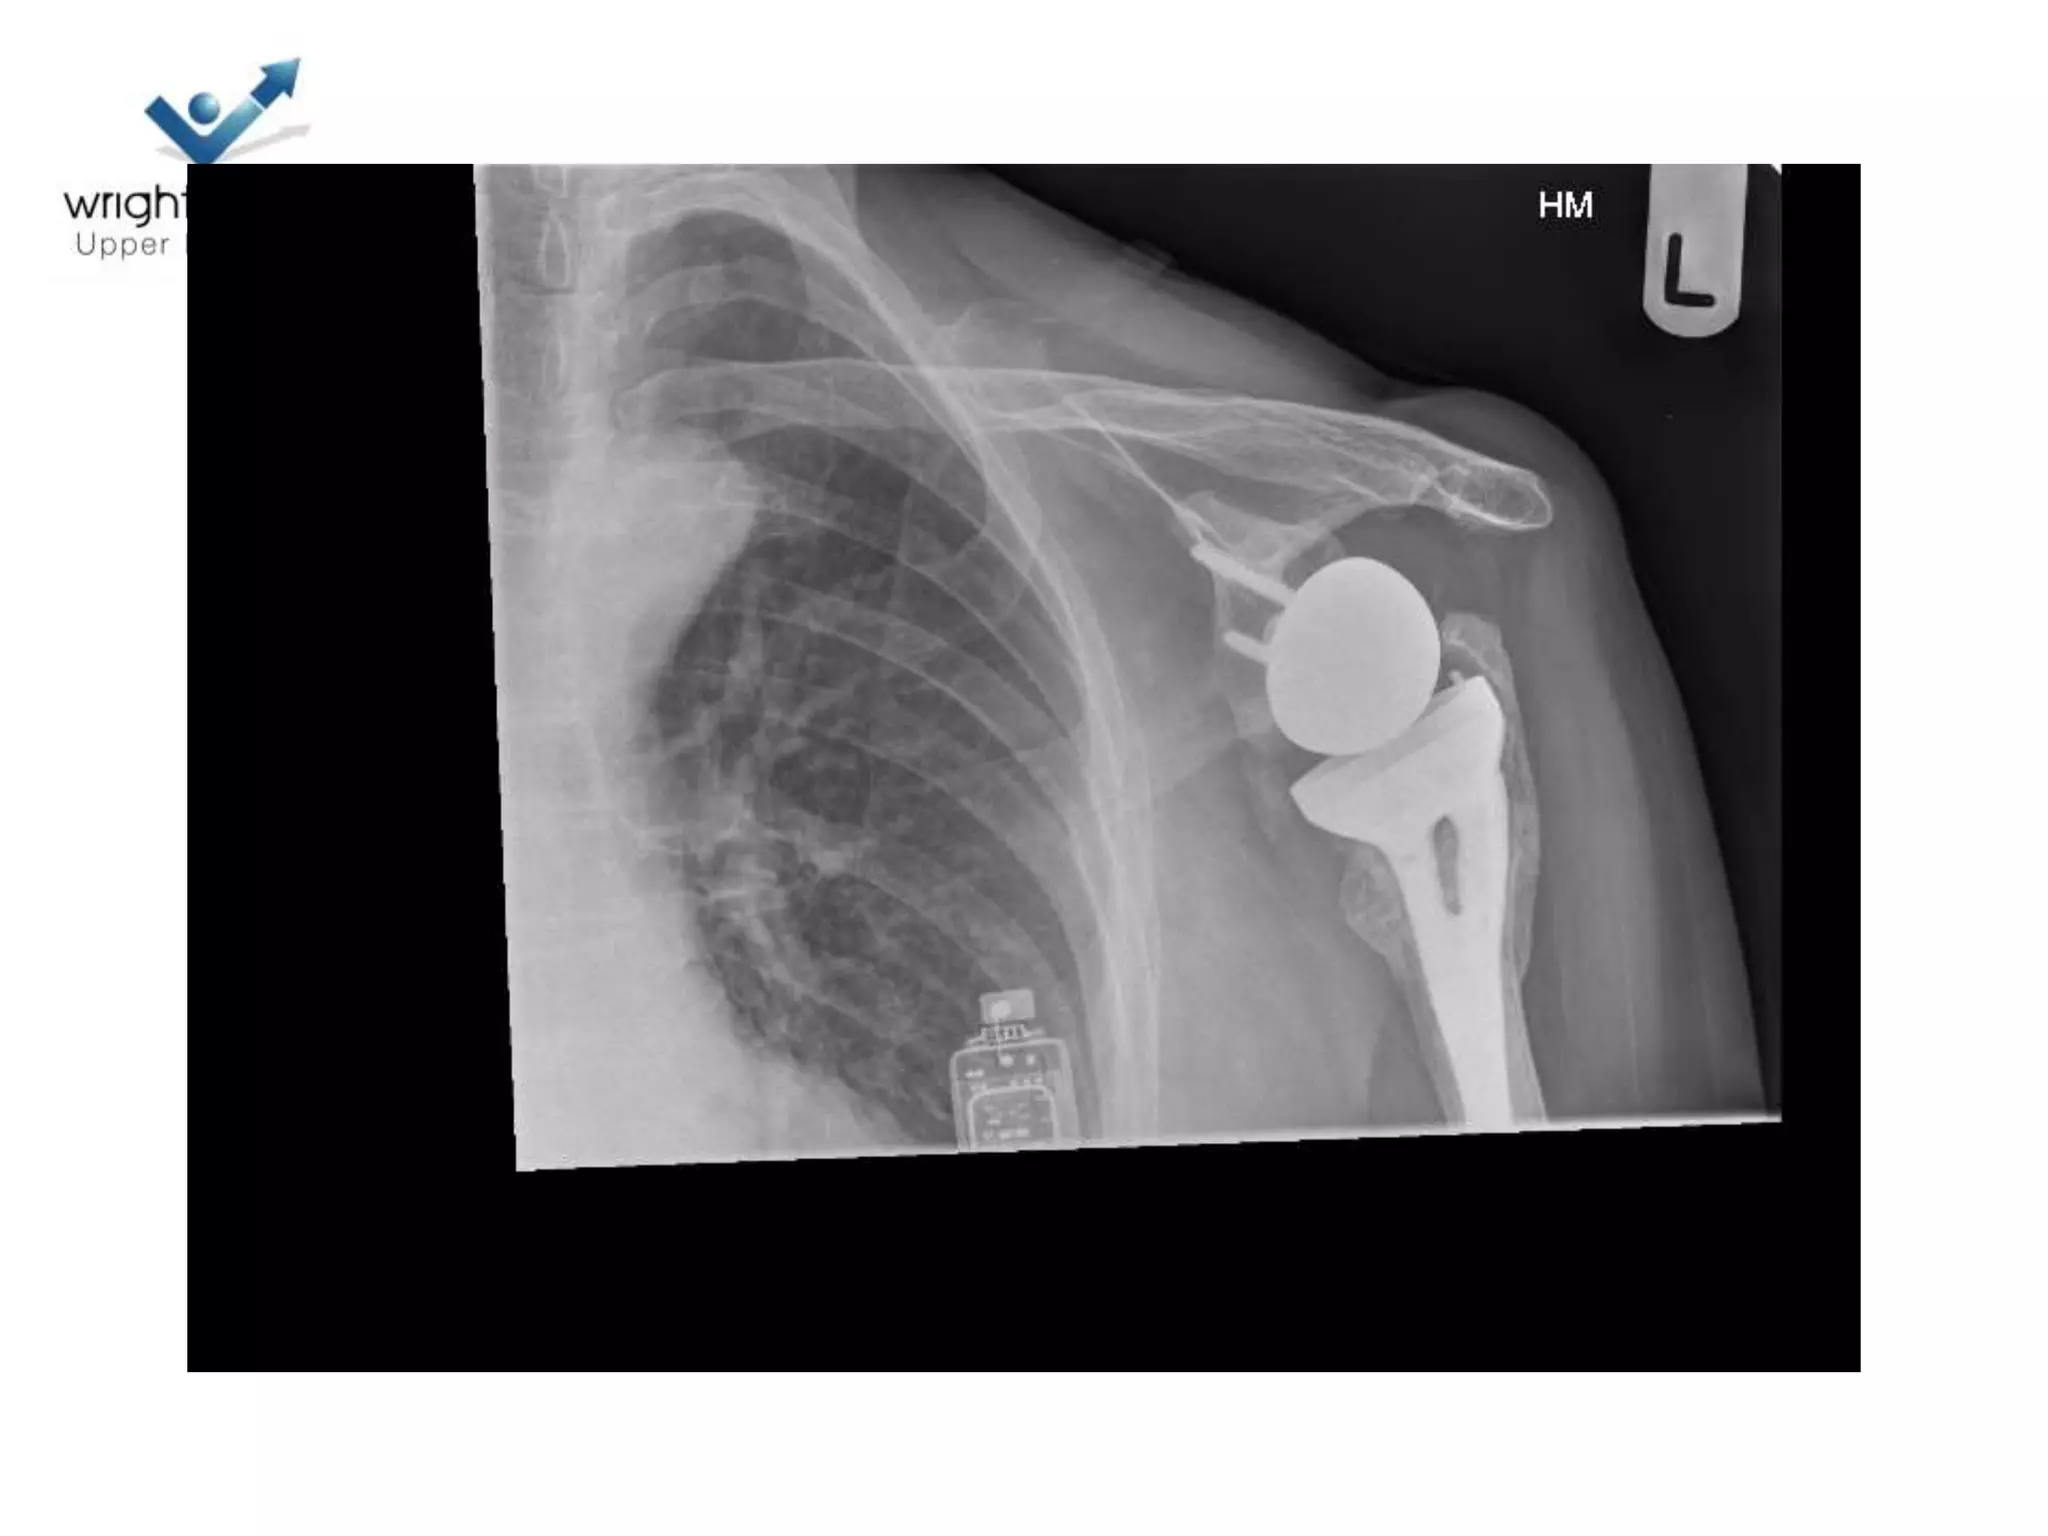

Hemiarthroplasty

• Getting it right

• Depth of prosthesis

• Version of prosthesis

• Size of the head